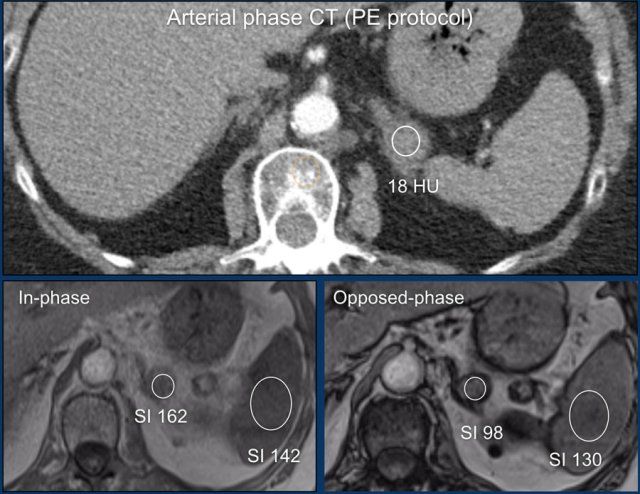

MRI performed for a left adrenal incidentaloma discovered on a non-contrast and arterial phase CT scan in a 61-year old male patient with an abdominal aneurysm.

On the non-contrast CT density was 18 HU.

T1 out-of phase image shows subtle inhomogeneous signal drop compared to in-phase.

Note that the fat-suppressed T1 does not help in the detection of microscopic intracellular fat.

This adrenal lesion was discovered on a pulmonary embolism scan.

Using the Adrenal MRI calculator the adrenal spleen ratio (ASR) and signal intensity index (SI-index) can be measured from ROIs placed inside the adrenal lesion and the spleen on both the in-phase and out-of-phase images.

Based on the signal intensities measured within ROIs placed over the adrenal lesion and spleen the ASR is 0,66 (< 0,71) and and the SII is 39,5% (> 16,5%), indicating that this is an adenoma.